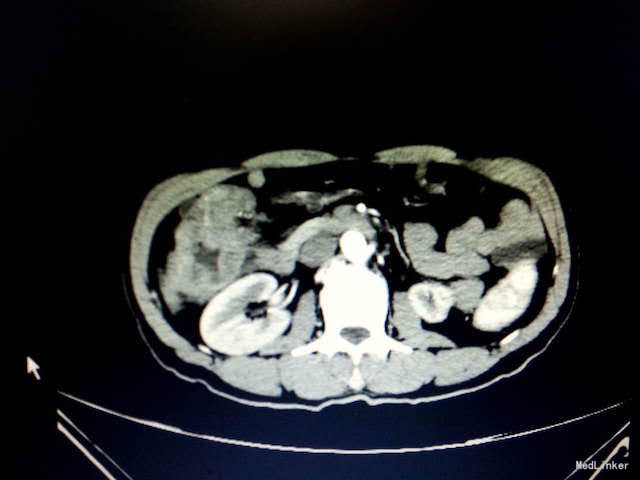

查体:消瘦体型,心肺查体阴性。腹软,右上腹深压痛,无反跳痛,未触及包块,肠鸣音正常。 辅助检查:入院血常规、生化、肝肾功、凝血、传染病未见明显异常。胃肠肿瘤指标正常。大便隐血试验(+)。腹部CT结果:结肠肝曲肠壁局部明显增厚,增强扫描强化明显,考虑恶性肿瘤,累及浆膜层(如下图所示)。

随访:术后病理结果:升结肠中-低分化腺癌,如下图。 讨论:鉴别诊断:胃肠道肿瘤:多见中老年,可反复腹痛,可出现排便习惯或性状改变,晚期可出现肠梗阻症状,也可表现为全身症状,考虑可能性大,CT、肠镜及活检结果可明确诊断。胆石症:常表现为右上腹绞痛,可反射至背部,可出现黄疸,多与进食油腻食物有关,超声及CT可有助鉴别。